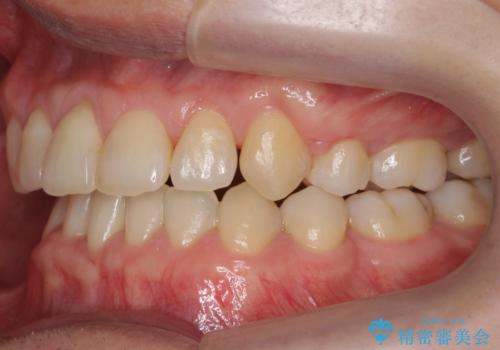

受け口 絶対に顎の手術はしたくない

- 受け口を主訴に来院。

下あごが大きく、顎の手術を含めた矯正をおすすめしましたが、手術は怖いので絶対にしたくないとのことでした。

歯並びのみを治す矯正は難しく、長期にわたる治療になるとご説明しました。

かみしめもあり、骨も固く、歯根も長いためなかなか歯が動かず、患者様も治療する側も忍耐を要する長期戦となりました。